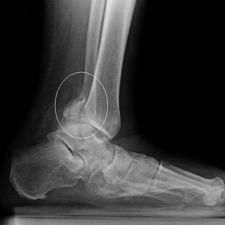

This 65-year-old insulin-dependent diabetic sustained a fracture of his right ankle in 2010 and had an open reduction internal fixation which failed due to problems with his healing. He went on to have a complete collapse of the right ankle and sought opinions on the options for him.

He was diagnosed as having a Charcot's Joint i.e. due to his diabetic status, he lost sensation in the foot and ankle area which eventually led to a collapse of the foot and ankle and resulted in poor wound healing and bone repair. These all led to his poor outcome from his primary surgery.